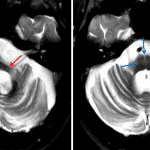

Cerebellar ataxia-type multiple system atrophy (MSA-C)

Sample ReportMarked pontocerebellar atrophy out of proportion to relatively mild supratentorial parenchymal volume loss. In combination with the finding of cruciform T2 signal hyperintensity in the pons at the level of the middle cerebellar peduncles (“hot crossed bun” sign), this appearance is most suggestive of cerebellar ataxia-type multiple system atrophy (MSA-C).